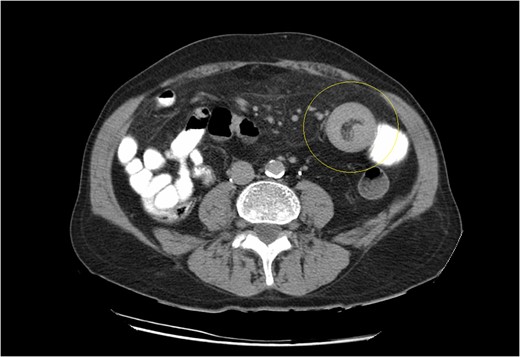

CT scan demonstrating the typical ‘doughnut’ sign of bowel intussusception.

Computed tomography is the modality of choice for diagnosis of an intussuscepted bowel loop, with a sensitivity and specificity of ~80% and 100%, respectively. Depending on sagittal or axial view, findings may include the presence of concentric rings due to duplication of small bowel layers (‘doughnut’ or ‘target’ sign), or a sausage shaped mass [3, 5, 6]. U/S scan is also useful for identification of intussuscepted bowel with the typical ‘target sign’ [6]. Diagnosis is usually set intraoperatively, because of the nonspecific clinical symptoms and non-pathognomonic radiological findings.